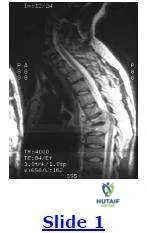

A clinical photograph (Slide 1) and radiographs (Slide 2) of a 13-year-old girl, who is neurologically normal, are presented. She does not report any pain. The most likely diagnosis is:

This patient has neurofibromatosis-1. She has a dystrophic scoliosis that is sharply angulated and involves only four vertebrae (Cobb levels T12-L3). The pedicles are thinned, and the endplates are scalloped. She also has subcutaneous neurofibromas.

This patient has neurofibromatosis-1. She has a dystrophic scoliosis that is sharply angulated and involves only four vertebrae (Cobb levels T12-L3). The pedicles are thinned, and the endplates are scalloped. She also has subcutaneous neurofibromas.

This patient has neurofibromatosis-1. She has a dystrophic scoliosis that is sharply angulated and involves only four vertebrae (Cobb levels T12-L3). The pedicles are thinned, and the endplates are scalloped. She also has subcutaneous neurofibromas.